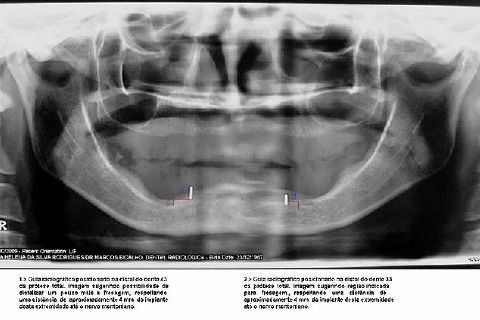

Protocolo Inferior com 5 Implantes - Parte I - Planejamento + Cirurgia

Apesar da boa adaptação e estética satisfatória, a principal queixa da paciente era a instabilidade da prótese inferior, como sempre ocorre nestes casos...atrofia do rebordo alveolar e perda da função mastigatória.